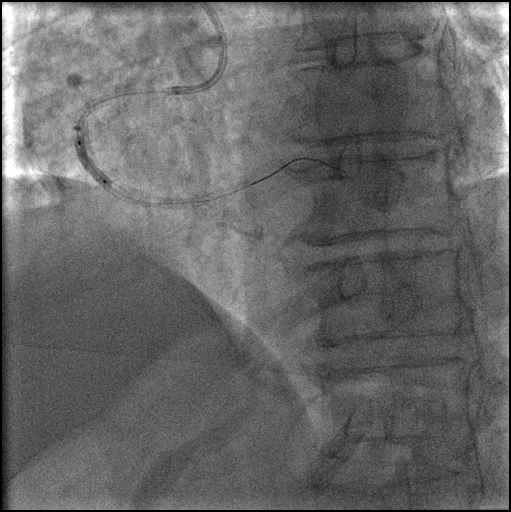

6F SAL1.0 GC, Finecross MGC,成功送入SION GW。

2.0x15mm, 2.5x12mm NC预扩张,球囊通过困难,改行旋磨术。

1.5mm 旋磨头 14万 RPM 旋磨6次。

6F Telescope™ 导引延长导管加强支撑。